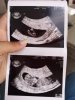

Ja już po wizycie... Wszystko oki. Lekarz powiedział, że są duże szanse na chłopca (fotka 1)

Załączniki

• IMG_20200817_174136.jpg